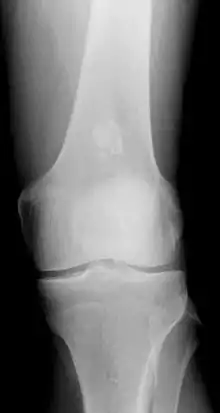

X-ray showing an enchondroma in the femur.

• x-ray – On plain film, an enchondroma may be found in any bone formed from cartilage. They are lytic lesions that usually contain calcified chondroid matrix (a "rings and arcs" pattern of calcification), except in the phalanges. They may be central, eccentric, expansile or nonexpansile.

Differentiating an enchondroma from a bone infarct on plain film may be difficult. Generally, an enchondroma commonly causes endosteal scalloping while an infarct will not. An infarct usually has a well-defined, sclerotic serpentine border, while an enchondroma will not. When differentiating an enchondroma from a chondrosarcoma, the radiographic image may be equivocal; however, periostitis is not usually seen with an uncomplicated enchondroma.